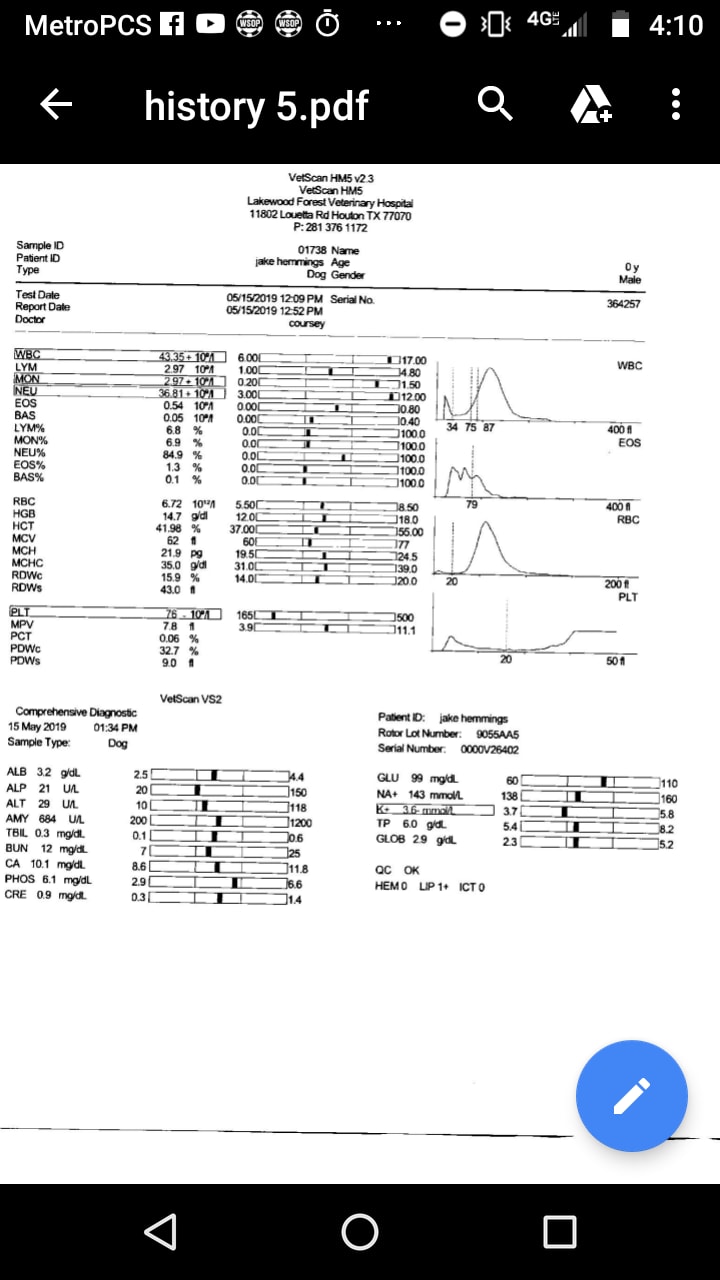

Getting diff answers. Notes from exam. Large mass encompassing colon, air distended, fistulas,could be rupturing bladder or prostate, blood pass from penis,rear right leg edema, testicles swollen, circulation compromised, diagnosed neoplasia colon,rectum possibly prostate. Recommend euthenasia.. A Dr here just told me he didn't see anything other than gas/ feces. Blood work and x rays attached